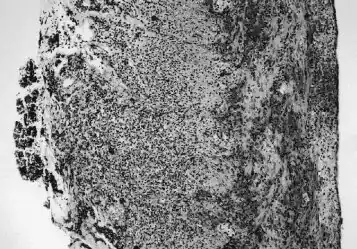

Histologic section demonstrating advanced necrotizing enterocolitis